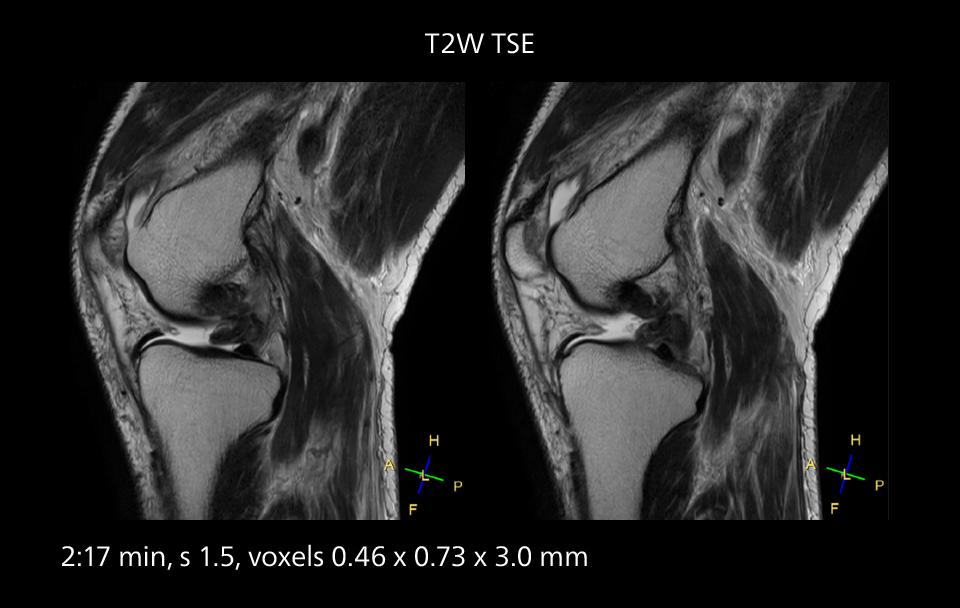

MRI of the knee

Images showing a posterior cruciate ligament (PCL) tear, a detached medial collateral ligament (MCL) on the tibial side and an intact anterior cruciate ligament (ACL). SmartPath to Elition X helped reduce scan time compared to previous imaging while maintaining resolution.

MRI of the knee

Images showing a posterior cruciate ligament (PCL) tear, a detached medial collateral ligament (MCL) on the tibial side and an intact anterior cruciate ligament (ACL). SmartPath to Elition X helped reduce scan time compared to previous imaging while maintaining resolution.